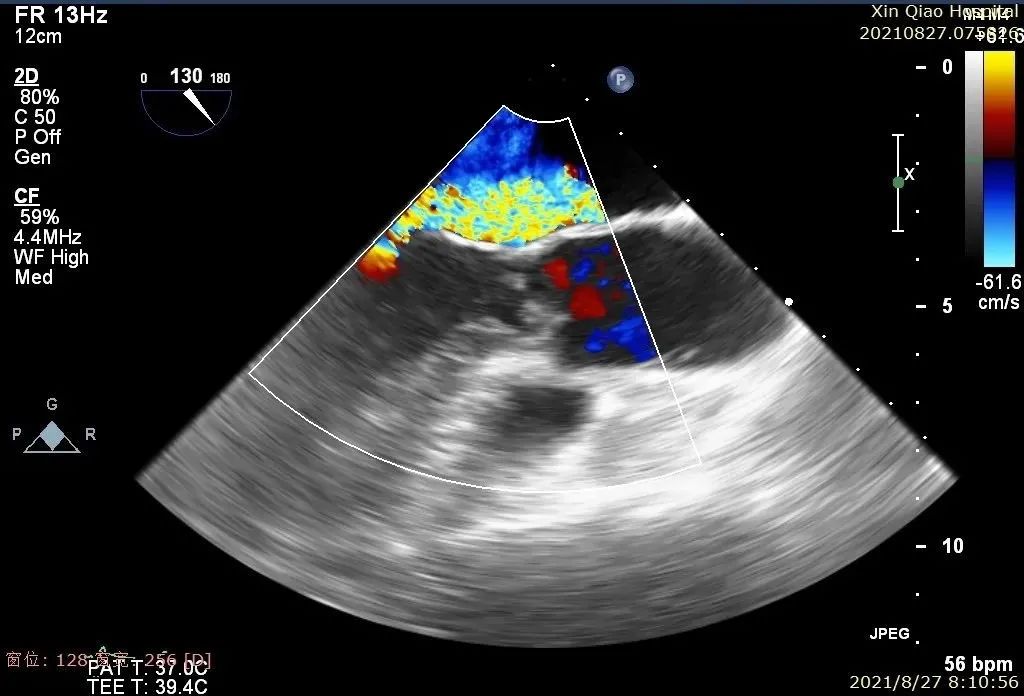

在麻醉和体外循环团队保驾护航下,器械经股静脉穿刺房间隔,通过输送系统送入患者左心房,到达二尖瓣膜反流处,在经食道超声及DSA引导下,术者通过反复评估二尖瓣膜脱垂范围、抓捕位置、反流程度,精准夹合,成功植入两枚DragonFly瓣膜夹。

术后即刻,患者反流显著减小,二尖瓣反流从4+减少到1+以下,左房压下降,血流动力学改善明显,手术取得了圆满成功。

术中超声

患者术后B超图